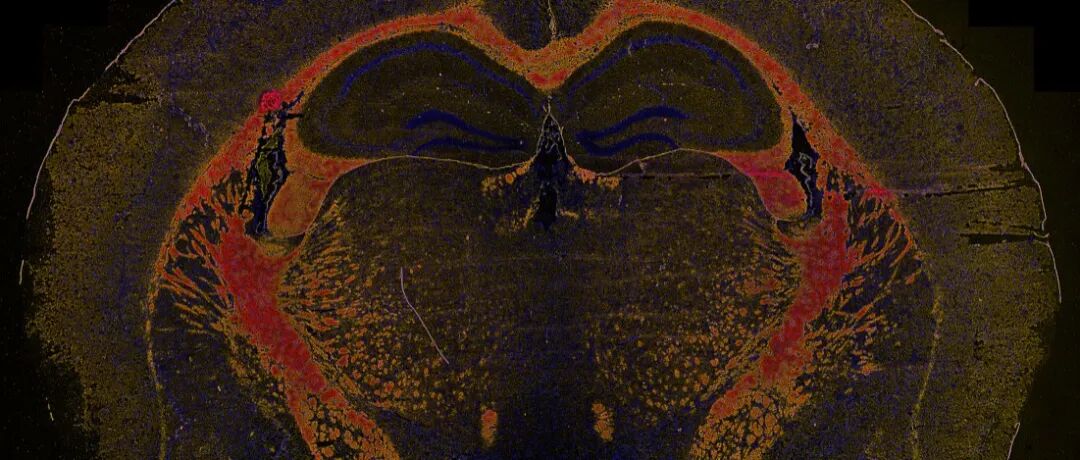

格物观癌:肿瘤浸润免疫的微观博弈